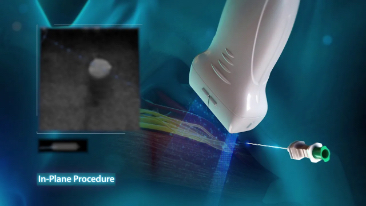

MindrayŌĆÖs Point of Care ultrasound machines provide leading-edge technology and everyday applications that meet the diverse demands of your departments and the evolving needs of your patient population. Our innovative, accessible Point of Care ultrasound solutions offer sophisticated tools and technologies that empower you to streamline workflow, minimize the risk of infection, and provide the highest quality of care now and in the future. Experience peace of mind and see something better with Mindray Ultrasound.